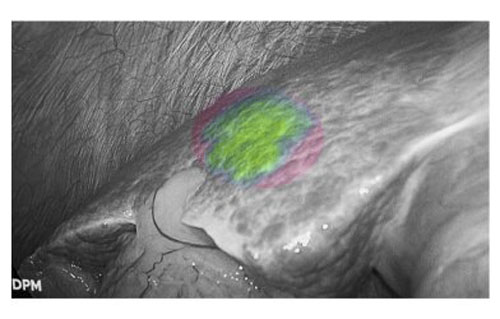

“隐匿”病灶无处遁形

肝癌患者多合并肝硬化背景,而腹腔镜手术因缺乏触觉反馈,致使术者在微创条件下难以识别隐匿性病灶。吲哚菁绿(ICG)荧光显影技术通过术前静脉注射造影剂,可精准定位3毫米的原发性肝癌和肝转移癌。该技术有效弥补了腹腔镜肝胆手术中触觉反馈缺失的固有缺陷,为微创精准外科提供了重要技术支撑。

荧光显影技术,可精确显示肝内隐匿病灶